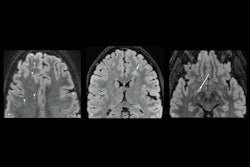

TORONTO - Diffusion spectrum imaging (DSI) is the preferred choice for MR imaging of mild traumatic brain injury, suggest findings presented June 2 at the International Society for Magnetic Resonance in Medicine (ISMRM) annual meeting.

DSI maps fiber architectures in brain tissues. The researchers highlighted that this method is a valuable tool for exploring brain structures and bridges micro- and macroscopic scales. DTI, meanwhile, detects how water travels along white-matter tracts in the brain.

Zhang and colleagues found that DTI had a higher mean diffusivity value in the brain injury group than the volunteer group when it came to the posterior limb of the right internal capsule (p < 0.05). However, after implementing tract-based spatial statistics, both DSI and DTI had comparable effectiveness in the posterior limb of the right internal capsule.

However, DSI showed advantages in other areas. The researchers also reported that doctors "subjectively" reported that DSI had higher image signal-to-noise ratio, clearer image quality, small whole-image distortion, and smaller mass area than those of DTI.